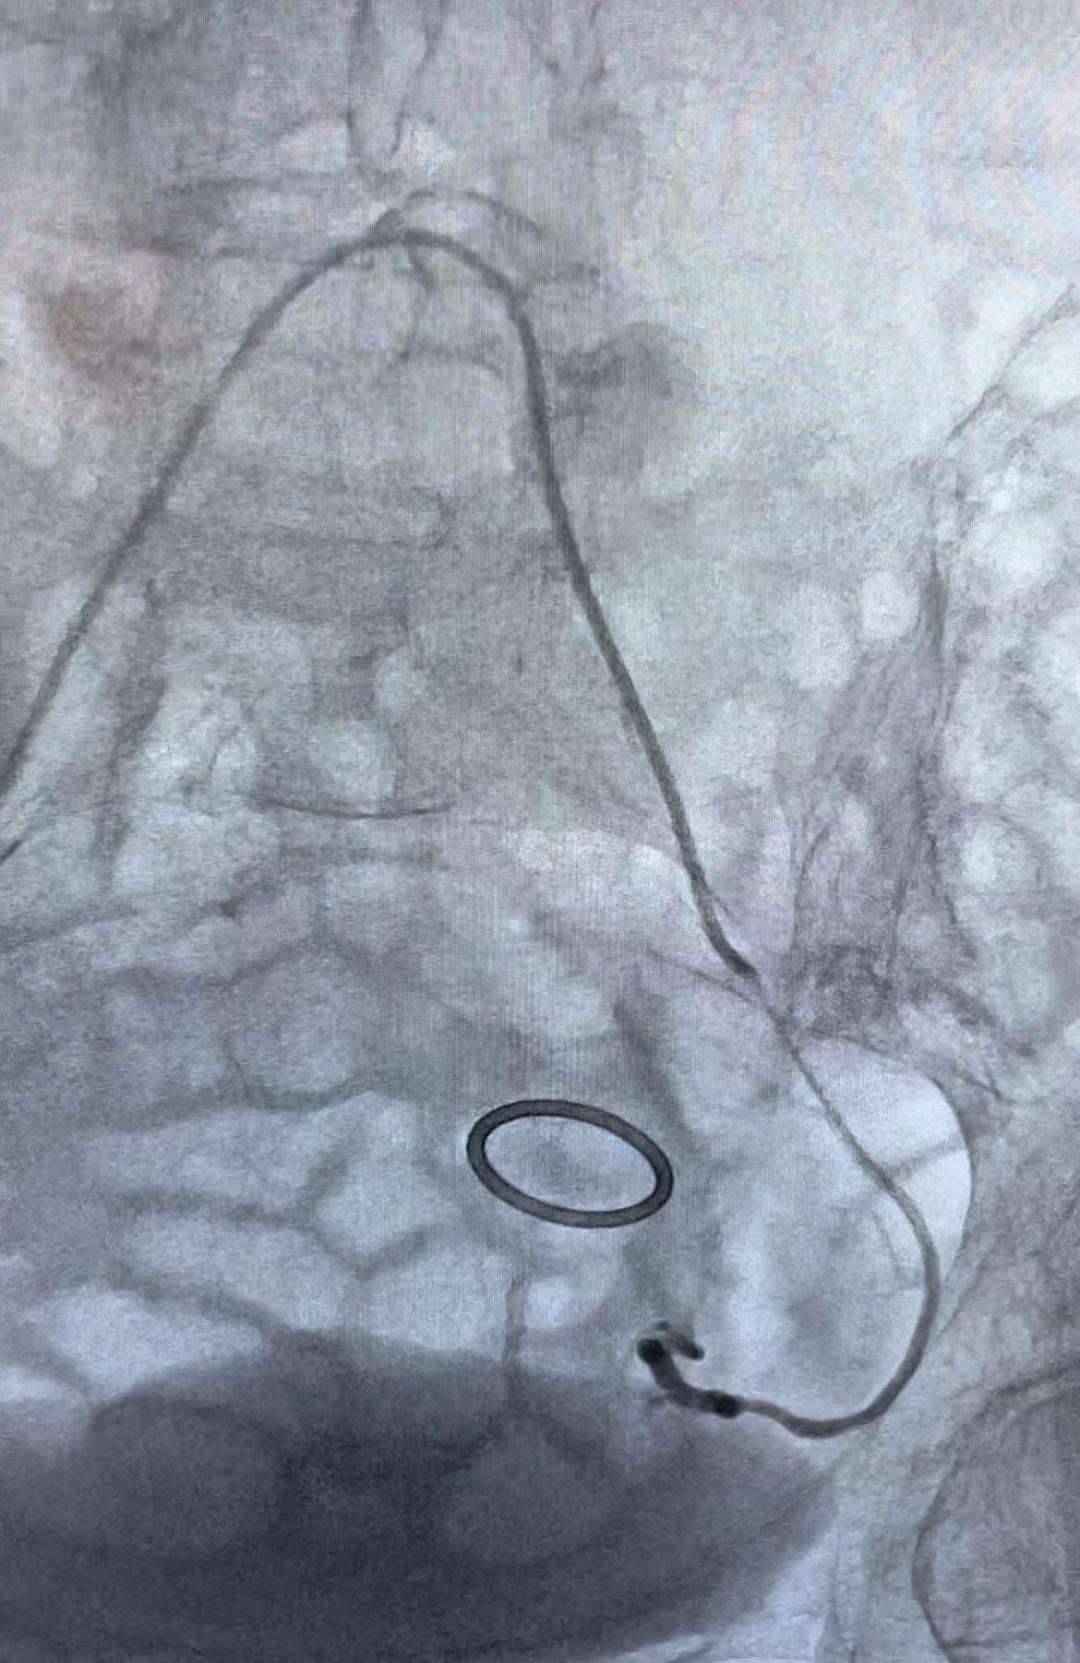

通过阴道填塞止血、药物止血,出血的问题解决得都不理想,肿瘤科马上参与到救治中来,肿瘤科鲍新医生会诊后评估,认为患者阴道流血时间长,同时,短期出血量进行性的增多引起了贫血并加重,考虑宫颈癌合并活动性出血,有大出血危及生命风险,有血管介入治疗止血指征,李岩与鲍新两位医生立即给患者施行了左右子宫动脉灌注化疗栓塞术,历时1小时,手术顺利完成。手术后,患者阴道流血明显减少,头晕和乏力的症状也明显缓解,可以安排后续的放化治疗方案。

栓塞前和栓塞后造影对比

栓塞前造影剂外溢显影

栓塞后造影剂外溢明显减少